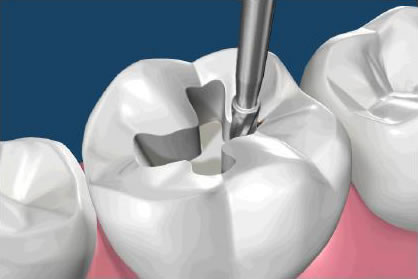

Zobozdravnik in pacient se dogovorita o načinu zdravljenja zob. V primeru, ko ostane zelo malo zobnega tkiva, se priporoča izdelava ustrezne zobne prevleke, ki v celoti prekrije zobni krn. Veliko je dejavnikov, ki lahko vplivajo na estetski videz, vzdržljivost in življenjsko dobo zalivk. Redni pregledi pri zobozdravniku pripomorejo k zgodnjemu odkrivanju zobne gnilobe, imenovane karies, preden se pojavijo težave. Z zobno gnilobo (kariesom) prizadeta trda zobna tkiva zobozdravnik odstrani do zdravega tkiva. Pri tem nastalo votlino (kaviteto) zapolni z zobno zalivko. Poznamo direktne in indirektne zobne zalivke.

Direktne zobne zalivke zobozdravnik dokončno izdela v ordinaciji, tu se odvijejo vse faze od odstranitve prizadetega tkiva, polnjenja, do dokončne obdelave. Glede na obseg odstranjenega obolelega tkiva so lahko eno, dve ali več ploskovne. Za izdelavo direktnih zalivk se lahko uporabi različen material.

Indirektne zobne zalivke so zalivke, izdelane v zobotehničnem laboratoriju po predhodnem odtisu pripravljene kavitete. Zobozdravnik odstrani obolelo tkivo, pripravi kaviteto, jo odtisne z odtisno maso, zobotehnik izlije delovni model in izdela zalivko, ki jo zobozdravnik nato zalepi – cementira v kaviteto. Te indirektne zalivke na stranskih zobeh (transkaninem področju) imenujemo inlay ali onlay. Indirektne zalivke iz estetskih materialov na vidnih površinah zob imenujemo zobne luske, ki so prav tako lahko izdelane iz različnih materialov.

Poškodovane zobne zalivke in tiste s slabo obrobno zaporo je treba zamenjati, da preprečimo ponovni pojav zobne gnilobe (sekundarni karies). Če tega ne upoštevamo, bo zdravljenje zahtevnejše, potrebno bo večje število obiskov pri zobozdravniku, zgodi pa se lahko tudi, da zob izgubimo. Obstaja veliko število materialov za izdelavo zalivk (amalgam in kompozit sta najpogostejša), vendar pa je dokončna odločitev, kateri je najbolj primeren, odvisna od posveta med zobozdravnikom in pacientom.